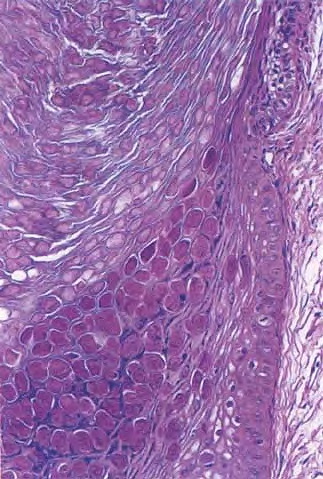

molluscum-contagiosum